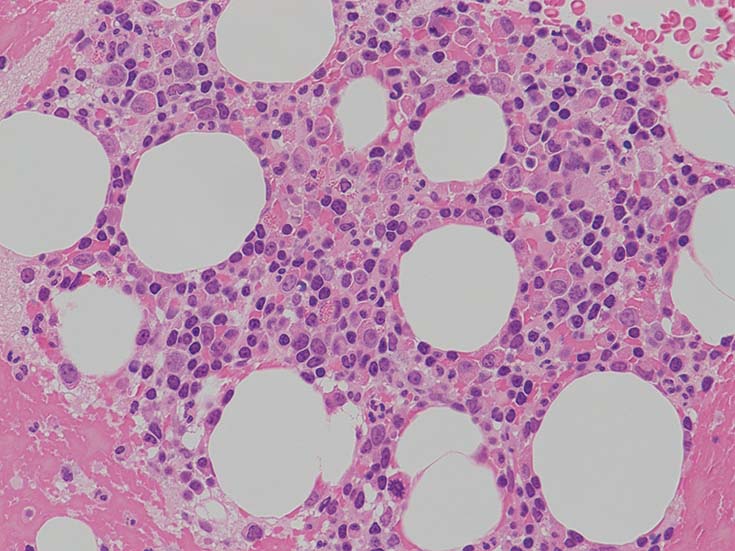

lymphoplasmacytic lymphoma(LPL)

検診異常の再検査で受診, 慢性炎症, 小球性貧血, 血清IgM高値あり. 造血器疾患を疑われ血液内科で精査となった.

IgG 1365mg/dl, IgA 225mg/dl, IgM 1800(35-220)mg/dl. 血清免疫電気泳動で IgM-λtype M proteinを検出. 尿中 Bence Jones タンパク-λ型(+).

この症例では骨髄組織での造血巣内にリンパ球や形質細胞の軽度増加があるようだが, 腫瘍細胞増殖が明瞭ではない. 結節形成はみられない. mast cellsの増加がNaphtol-ASD-CAE染色で確認される.